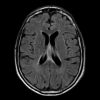

Lymphoma

» Thông tin: Nữam giới – 60 tuổi.

» Lâm sàng: Rối loạn tri giác.